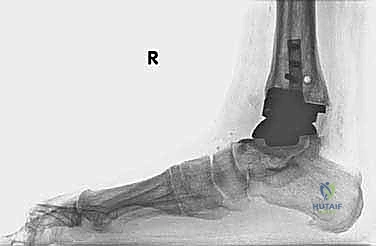

مراجعة مفصل الكاحل الصناعي هي إجراء جراحي ضروري لمعالجة المشاكل التي قد تنشأ بعد الجراحة الأولية، مثل كسور الكعبين أو عدم استقرار المفصل. يتضمن العلاج التشخيص الدقيق عبر الأشعة السينية والتصوير المقطعي، يليه التدخل الجراحي لتثبيت الكسور واستعادة وظيفة الكاحل، مع التركيز على التعافي المبكر.

- الأشعة السينية مع تحميل الوزن (Weight-bearing X-rays): لتقييم الزوايا الميكانيكية وتحديد مدى هبوط المفصل أو وجود كسور في الكعب.

كسور الكعبين (Malleolar Fractures) المصاحبة للمفصل الصناعي

من أعقد التحديات التي تواجه جراحي العظام هي حدوث كسور في الكعب الداخلي (Medial Malleolus) أو الخارجي (Lateral Malleolus) في وجود مفصل صناعي. تحدث هذه الكسور لعدة أسباب:

1. ترقق العظام: حول المفصل الصناعي نتيجة لعدم استخدام الطرف بشكل طبيعي (Stress Shielding).

2. الاصطدام الميكانيكي (Impingement): إذا كان حجم المفصل الصناعي أكبر من اللازم، فقد يضغط على الكعبين من الداخل ويؤدي لكسرهما بمرور الوقت.

3. الإصابات المباشرة: مثل السقوط أو التواء الكاحل.

علاج هذه الكسور يتطلب مهارة فائقة من الدكتور محمد هطيف، حيث يتم استخدام تقنيات الجراحة الميكروسكوبية وتثبيت الكسور باستخدام صفائح معدنية دقيقة ومسامير (Locking Plates) دون المساس بثبات المفصل الصناعي، أو يتم دمج علاج الكسر ضمن عملية مراجعة المفصل الكلية إذا كان المفصل نفسه تالفاً.